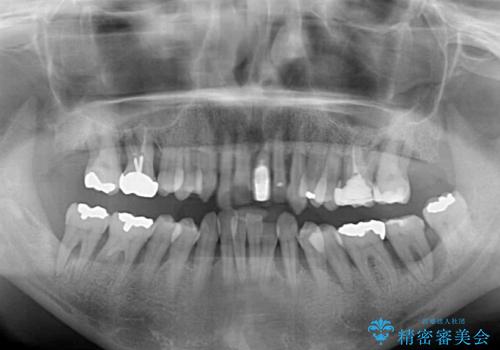

歯周病でグラグラの歯 矯正治療と歯周外科を併用した総合歯科治療

- 近医に通い続けるも、一向に不快感が改善しないとのことで来院された患者様です。

診察を行ったところ、重度歯周病の状態の上に上下の歯列が著しい叢生という状態でした。

歯周初期治療として抜歯や歯槽骨再生治療を行い、さらに歯周ポケット除去を行った後に矯正治療で歯列を整えて行くこととしました。